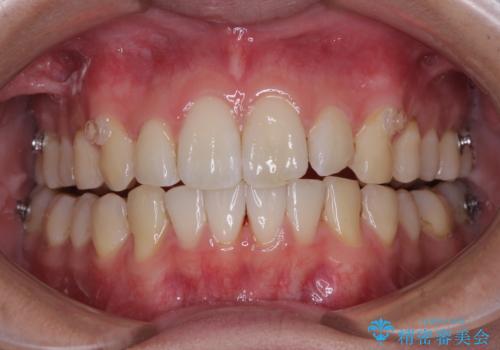

前歯のデコボコをインビザラインで綺麗に改善

- 上下前歯のデコボコとクロスバイトを気にして来院された患者様です。

インビザラインを用い、IPR(歯と歯の間を削る)と歯列全体を拡大させることで、歯並びを整えていくこととしました。

毎日22時間の装着時間を徹底してくださったのですが、左右ともに臼歯が咬合しなくなるという、インビザライン独特の症状が強く長く続いてしまい、終了するまでに長期間を要してしまいました。